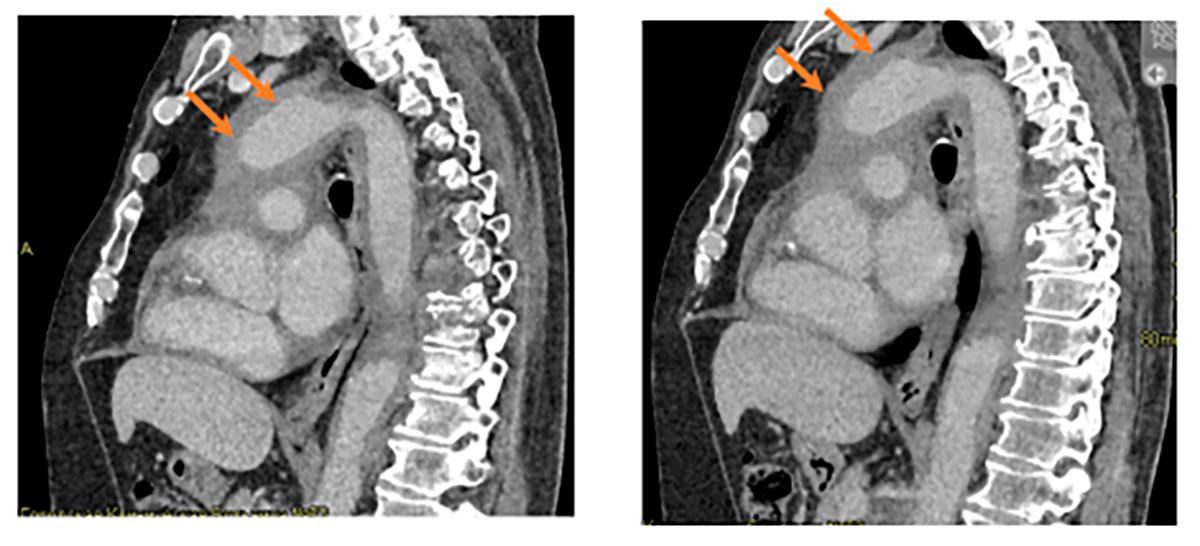

Пациент был выписан на амбулаторный этап наблюдения. Принято решение об инициации терапии вемурафенибом 240 мг х 2 раза в день внутрь. С 20.10.2023 начата терапия. Пациент по данным Единой Электронной Медицинской карты продолжает амбулаторно прием вемурафениба на протяжении более года. Исходя из осмотров гематолога — явления дыхательной недостаточности не беспокоят. Эпизодов гипертермии нет. Выполнялись контрольные КТ ОГК и ОБП с контрастным усилением на фоне проводимой терапии —картина нелангергансоклеточного гистиоцитоза (болезнь Erdheim-Chester), положительная динамика на фоне лечения, с уменьшением выраженности периваскулярной инфильтрации аорты и ее ветвей, уменьшением инфильтрации забрюшинного пространства. Регресс признаков хронического экссудативного перикардита. Уменьшение (нормализация) размеров почек, двусторонний гидронефроз, обусловленный компрессией мочеточников и правой лоханки инфильтратом. Нефростомические дренажи с обеих сторон. Регресс перипортального отека (см. рис. 4-6).

Рис. 4. Циркулярная инфильтрация вокруг восходящего отдела аорты (аорта окружена муфтообразной тканью) — синдром «обложенной» аорты, coated aorta sign. Слева 2025 год, справа 2023 год.

Сагиттальная проекция.

Рис. 5. Утолщение паранефральных перегородок с обеих сторон по типу «волосатых» почек (“hairy” kidney). Слева 2025 год, справа 2023 год. Аксиальная проекция.

Рис. 6. Инфильтрация забрюшинной клетчатки, положительная динамика. Слева 2025 год, справа 2023 год. Аксиальная проекция.